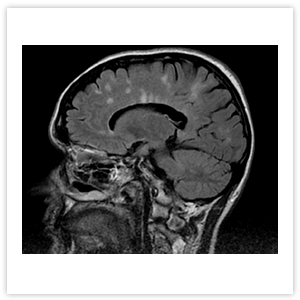

На МРТ головного мозга при РС выявляются множественные очаги, расположенные в белом вещества головного мозга и рядом с корой (Рисунок 4). При ОНМ на МРТ головного мозга изменений может не быть, а если они обнаруживаются, то опытным специалистом лучеой диагностики могут быть замечены отличия от очагов рассеянного склероза (Рисунок 5).

Рисунок 4. МРТ головного мозга пациента с РС: множественные очаги демиелинизации в лобной, теменной и затылочной долях головного мозга